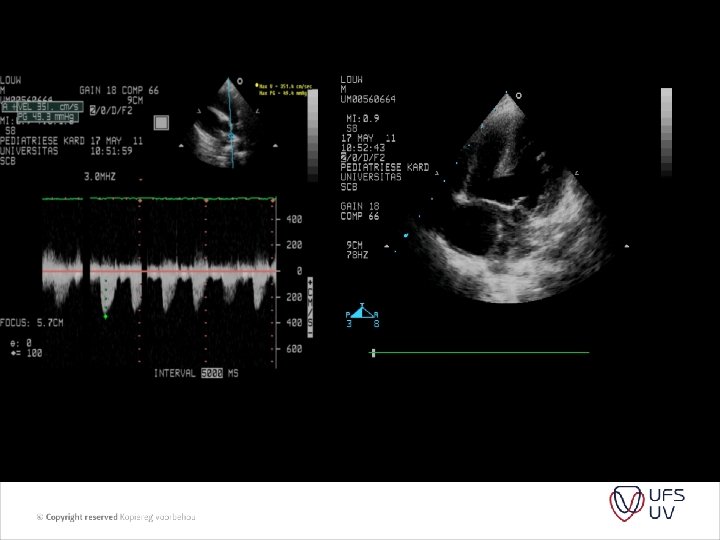

PVR = PAP/ PAflow Substitude PA pressure with TR jet Substitude PA flow by RVOT VTI (velosity time integral) And we get PVR = TR jet velocity/ RVOT VTI x 10

• • Figure 1 Images showing peak tricuspid regurgitant velocity (TRV) and right ventricular outflow time-velocity integral (TVIRVOT) in a patient with normal pulmonary vascular resistance (PVR). (A) TRV is 2. 86 m/s. (B) TVIRVOT is 20. 8 cm. The ratio of TRV/TVIRVOT = 2. 86/20. 8 = 0. 1375. . This patient’s invasive PVR measurement was within 0. 4 WU of the echocardiographic value (PVRCATH = 1. 3 WU). PVRECHO = PVR in WU calculated based on the linear regression equation in which a value for PVR in WU was modeled based on TRV/TVIRVOT. PVRCATH = invasive PVR.

• Figure 2 Images showing TRV and TVIRVOT in a patient with elevated PVR. (A) TRV is 3. 64 m/s. (B) TVIRVOT shows a clear deceleration of pulmonary flow before the pulmonic valve closure click and is calculated at 6. 5 cm. The ratio of TRV/TVIRVOT = 3. 64/6. 5 = 0. 56. . This patient’s invasive PVR measurement is also within 0. 4 WU of the echocardiographic value (PVRCATH = 6. 0 WU). Abbreviations as in Figure 1. • • J Am Coll Cardiol, 2003; 41: 10211027